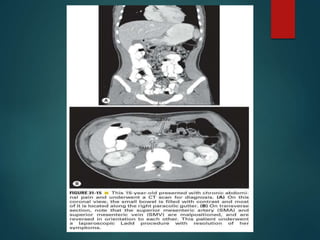

Contrast X Ray •Delineation of the duodenojejunal junction remains the most important diagnostic tool. • The duodenum should be seen traveling across the spine to the left. • Additionally, the lateral film will show the duodenum obtaining a retroperitoneal, posterior position.

• 32.

• Abnormal findingsinclude – positioning of the duodenojejunal flexure to the right of the spine, obstruction of the duodenum – The “coil spring,” “corkscrew,” or “beak” appearance of the obstructed proximal jejunum • Double-bubble sign in acute duodenal obstruction. • Gasless abdomen in midgut volvulus (gut is filled with fluid)